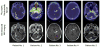

Increased human epidermal growth factor receptor 2 (HER2) expression is a hallmark of aggressive breast cancer. Imaging modalities have the potential to diagnose HER2-positive breast cancer and detect distant metastases. The heterogeneity of HER2 expression between primary and metastatic disease sites limits the value of tumor biopsies. Molecular imaging is a noninvasive tool to assess HER2-positive primary lesions and metastases. Radiolabeled antibodies, antibody fragments, and affibody molecules devise a reliable and quantitative method for detecting HER2-positive cancer using PET. HER2-targeted PET imaging is a valuable clinical tool with respect to both the care and maintenance of patients with breast cancer.